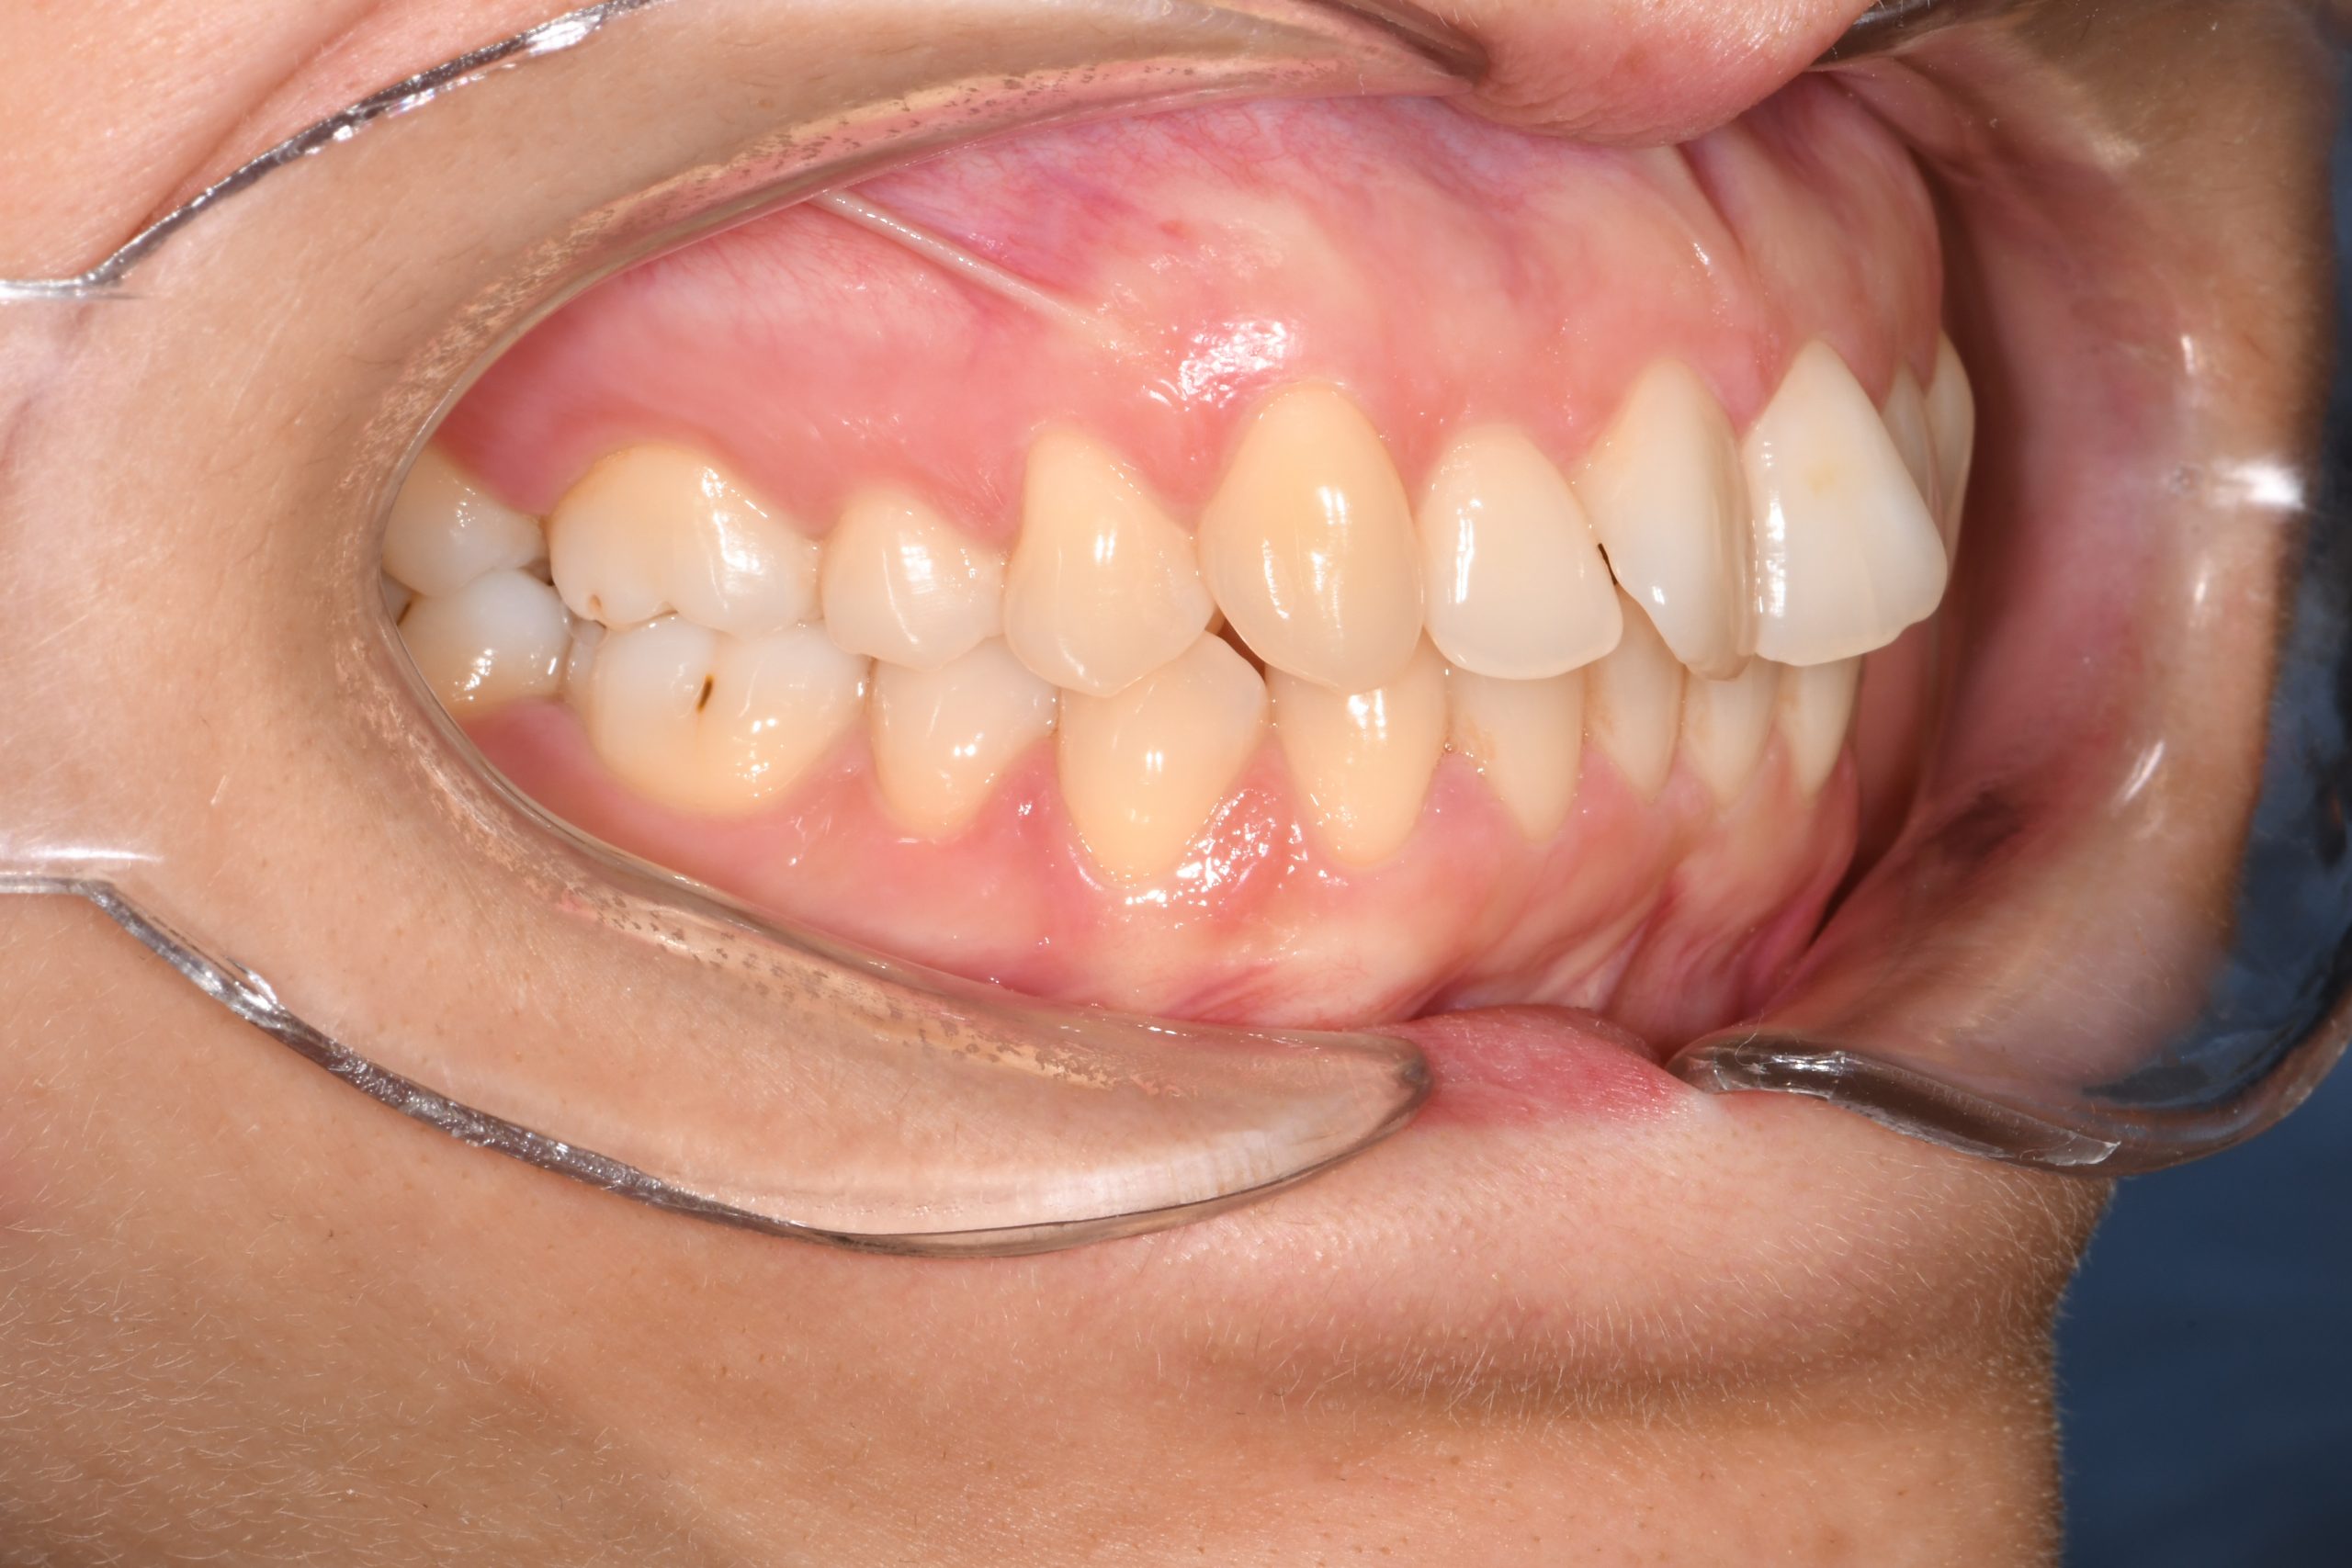

Az elmúlt évekből rengeteg szakmai referenciát tudnánk bemutatni, amelyek különböző fogszabályozási problémákat oldottak meg. Válogatva a több száz esetből, ezen az oldalon olyan képeket, információkat igyekeztünk bemutatni, amelyeknek a segítségével a jövőbeni pácienseinknek azt tudjuk üzenni: A Te fogsorod is lehet gyönyörű!

(Képeket a Pácienseink külön írásos beleegyezésével mutatjuk be!)